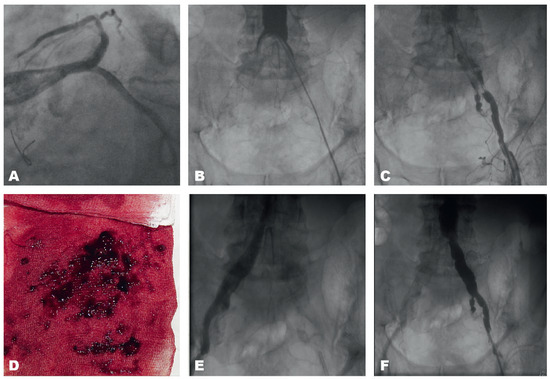

Acute Leriche Syndrome in an 83-Year-Old Man with Non NSTEMI After Cardiac Resuscitation Because of Ventricular Fibrillation

by Daniel Sürder, Jos C. van den Berg, Tiziano Moccetti and Giovanni B. Pedrazzini

An 83-year-old man on permanent haemodialysis was admitted to the emergency department in cardiogenic shock after prolonged electromechanical resuscitation because of ventricular fibrillation [...] Full article